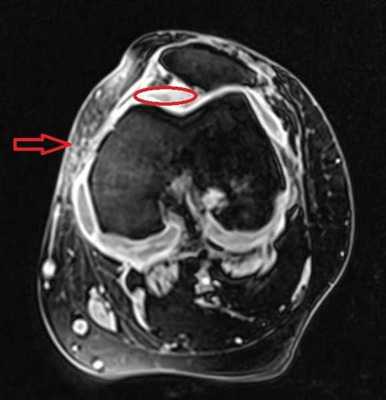

МРТ коленного сустава. На МР-томограмме в аксиальной плоскости определяется яркий МР-сигнал от жидкости: отечность мягких тканей (стрелка) и жидкость в полости сустава (обведено).

«На серии томограмм картина выявлена латеропозиция надколенника, повреждения медиального удерживателя и хондромаляция хряща последнего. Умеренный посттравматический отек тела Гоффа. Экссудативный синовит. Бурсит инфрапателлярной сумки. Умеренный отек мягких тканей в подколенной области».